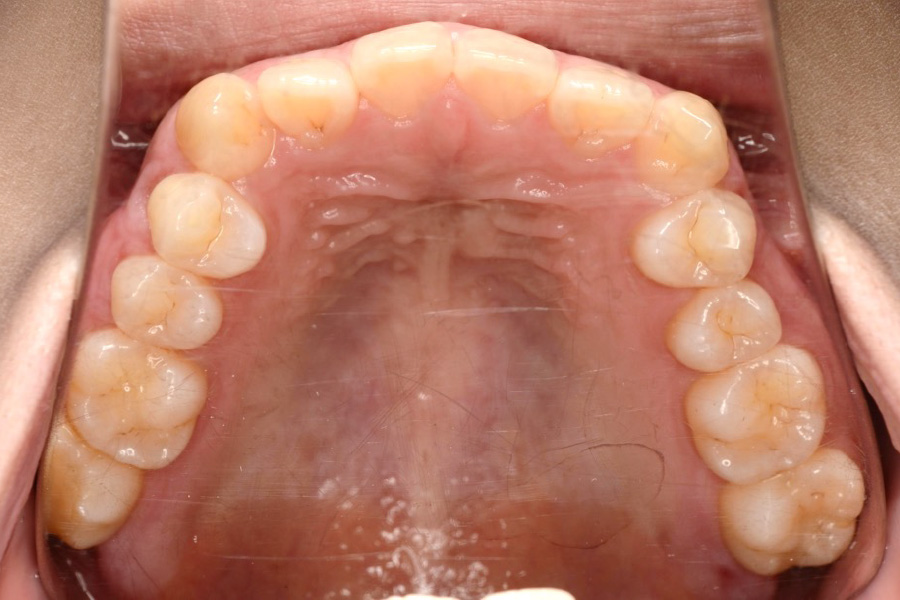

【20代女性】

全体のガタつきを

インビザライン矯正で治療したケース

治療前

主訴 全体のガタつきが気になる

治療内容 インビザライン矯正

非抜歯